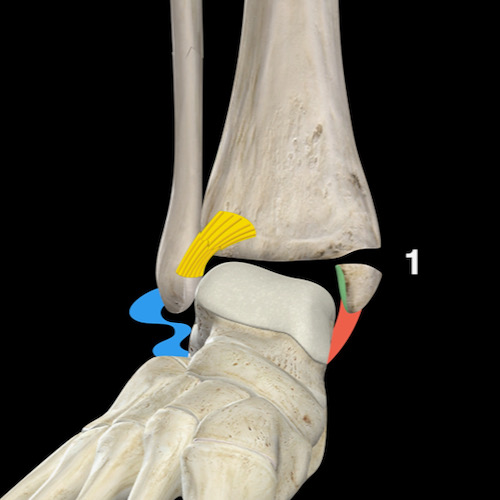

Bước 2 – Đây có phải là gãy xương Weber B / SER không?

Nếu không phải là gãy xương Weber A, câu hỏi tiếp theo cần đặt ra là: đây có phải là gãy xương Weber B không?

Khi phát hiện gãy xương Weber B — vốn luôn hiện rõ trên tư thế chụp thẳng (AP) hoặc tư thế chụp nghiêng — điều duy nhất cần kiểm tra là liệu có tổn thương giai đoạn 3 không ổn định với tổn thương phía sau, hay thậm chí giai đoạn 4 với tổn thương phía trong hay không.

Cuộn qua các hình ảnh để thấy cách tổn thương diễn tiến theo một trình tự cố định theo chiều kim đồng hồ.

Mọi thứ trở nên rất đơn giản khi bạn ghi nhớ trình tự cố định của các tổn thương:

- Phía trước

Lực căng tại khớp chày mác trước (syndesmosis trước) gây đứt dây chằng hoặc bong điểm bám tại xương chày — gãy xương Tillaux. - Phía ngoài

Lực xoay ngoài tác động lên xương mác gây ra đường gãy chéo — gãy kiểu đẩy ra sau (push-off fracture). - Phía sau

Khi xương sên đẩy mảnh xương mác về phía sau, lực căng tại khớp chày mác sau (syndesmosis sau) sẽ gây đứt dây chằng hoặc bong mắt cá thứ ba (malleolus tertius). - Phía trong

Khi xương sên tiếp tục di chuyển ra sau ngoài, lực căng rất lớn tác động lên dây chằng bên trong (dây chằng delta) sẽ gây đứt dây chằng hoặc bong mắt cá trong.